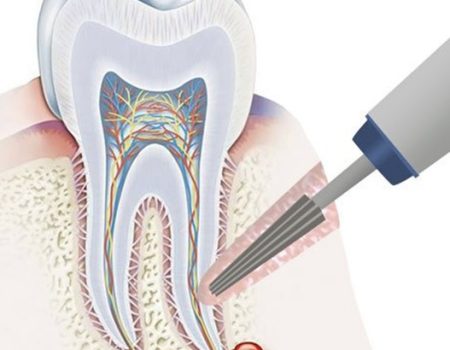

4. Зріз кореня. Хірург відсікає пошкоджену частину кореня та видаляє запалені тканини (гранульому або кісту).

5. За необхідності канал пломбують через верхівку.